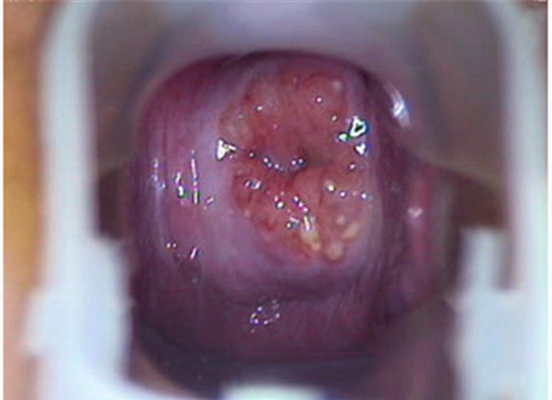

重度宮頸糜爛圖 (22)